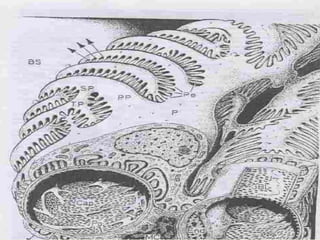

Nefron

 Böbrek cisimciğinden ve onu saran Bowman

kapsülünden meydana gelen süzme birimidir.

 Bowman kapsülü  İki tabakası var  Kapiller

glomerüle tutunan visseral ve bağ dokusu stromasına

bitişik pariyetal tabaka.

 Visseral tabaka  Podosit denilen ve bir bazal laminaya

oturan epitel hücreleriyle döşelidir.

 Pariyetal tabaka  Basit yassı epiteli destekleyen bir

bazal laminayla kuşatılır ve proksimal tübülün basit kübik

epiteliyle devam eder.

Glomerül

Üç bileşeni vardır:

- Glomerüler kapiller  Pencereli epitelle

döşelidir

- Mezanjiyum  Mezanjiyal matrikse gömülü

mezanjiyal hücrelerce oluşturulur.

- Podositler  Bowman kapsülünün visseral

tabakasını meydana getirirler.

Podositler

 Glomerüler süzme bariyerini  Podostiler ve pencereli

endotel hücrelerinin her ikisi ve bunların ilişikte olduğu

bazal lamina oluşturur.

 Aynı podositten veya komşu podositlerden hücre

uzantılarının sonlanmaları olan pediseller, bazal laminayı

kaplamak için birbirlerinin içine girerler ve süzme

yarıkları olan boşluklarla ayrılırlar.

 Pediseller  Bazal laminaya α3β1 integrinle tutunurlar.

 Süzme yarığı diyaframı, aktin filamentlerine CD2AP

proteiniyle tutunan “nefrin” proteininden oluşur.